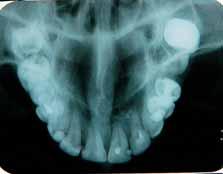

Case 2:

A 20 year old male was referred to Endodontic Department of Jahra Dental Speciality Centre for root canal treatment of lower right first mandibular molar. The referring dentist had done pulpotomy of the tooth. On examination, the tooth was slightly tender on percussion. Patient had no other symptoms and medical history was non contributory. Preoperative radiograph showed mandibular molar with one mesial and two distal roots. The distal root was with additional distolingual root. (Figure 5). Endodontic procedure was carried out under local anesthesia and rubber dam isolation. Initially two mesial and two distal canals were detected. The distal canal orifice was wide and opened to two separate canals. In mesial root after initial debridement of two canals, a bleeding spot remained in between the two canals which led to further exploration with a K file #08 and subsequently an intermediate canal was located. (Figure 6). Working length radiograph with distal angulation showed three mesial canals and two distal canals. (Figure 7). All the five canals were negotiated, working length determined, biomechanical preparation was carried out followed by obturation. (Figure 8). The patient was followed up.

Figure 1- Pre operative radiograph showing distal caries. Figure 2- Pulp chamber floor showing three independant mesial and two distal orifices. Figure 5- Pre operative radiograph showing mesial root and a distal root with an additional indistinct distolingual root. Figure 6- Pulp chamber showing three mesial and two distal canal orifices. Figure 7- Working length radiograph taken with distal shift technique. Figure 8- Post operative obturation radiograph showing three mesial and two separate distal roots. Figure 3 - Working length radiograph reveals three canals in the mesial root and two canals in the distal root. Figure 4- Post operative obturation radiograph.